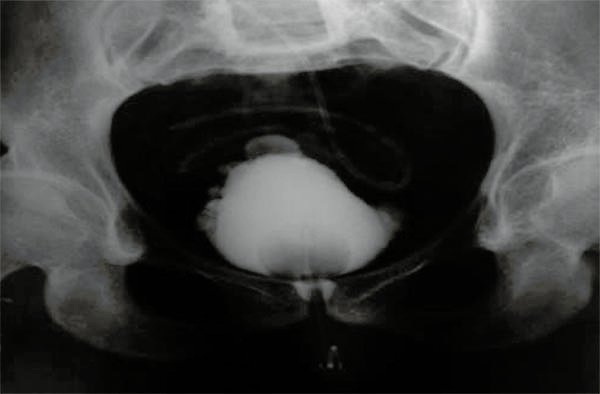

Figura 3:

Cistografía paciente n°5.